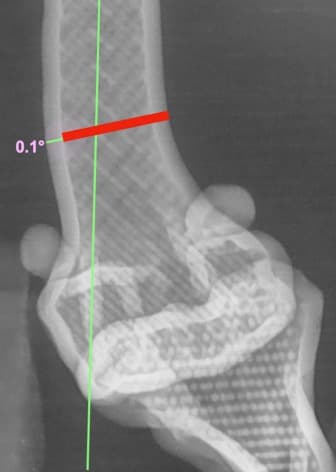

13수술 중 골절 상태 혹은 이식물 적용 후 상태 등 육안으로 명확히 확인하기 힘든 상태를 X-ray 확인하여 정확한 수술 결과를 만들어 내는 것이 가능